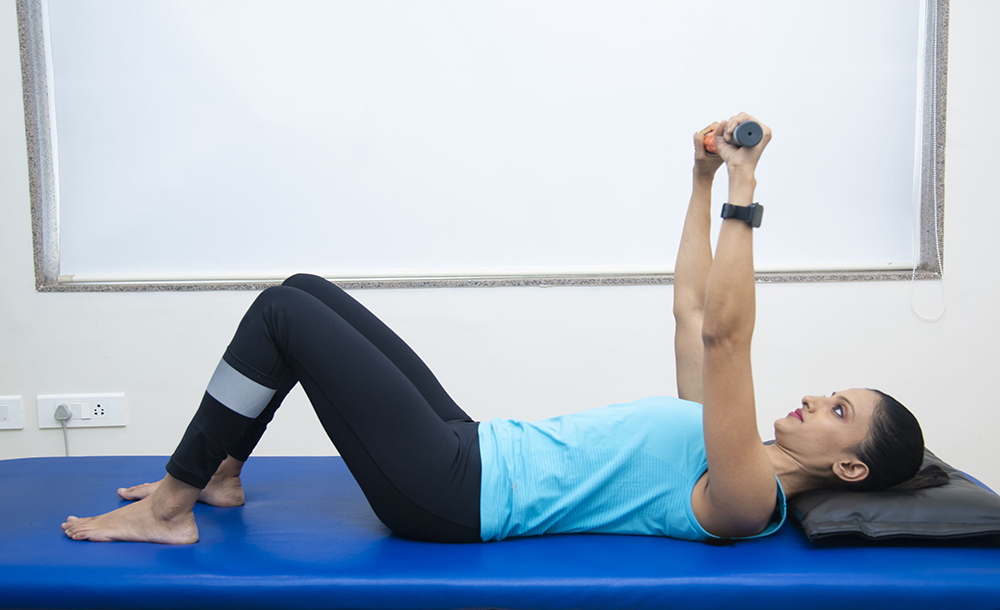

Shoulder rehab is a type of general conditioning program that is designed to provide a vast array of exercises designed to assist individuals after experiencing an injury or having surgery. It aids in ensuring that person is able to quickly return to their daily activities.

We have SKC(Shoulder Knee Clinic) Shoulder Rehab Treatment Package, specially designed to treat shoulder related injuries.